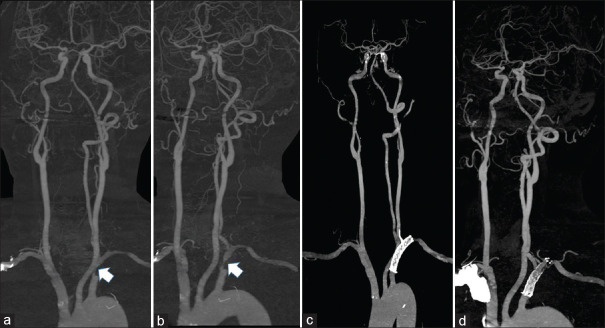

Successful subclavian artery stenting in a patient with subclavian steal syndrome associated with contralateral vertebral artery hypoplasia.

锁骨下窃断综合征伴对侧椎动脉发育不全患者的锁骨下动脉支架置入术成功。